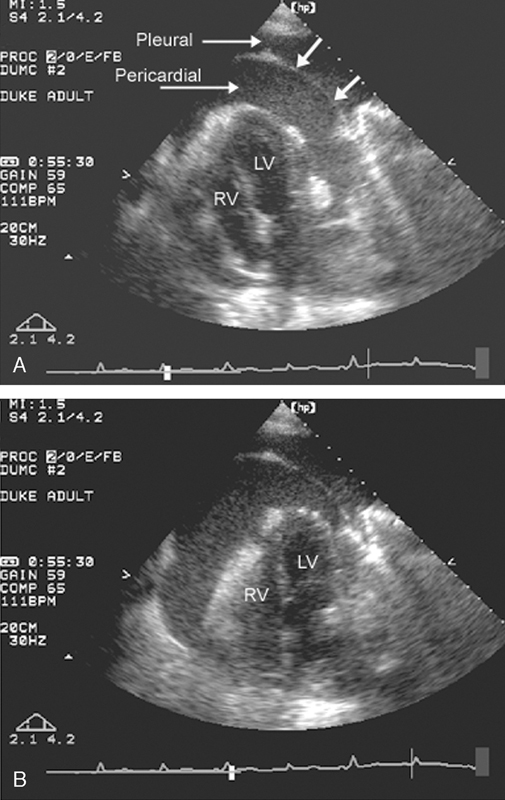

فحوصات تشخيصية لبعض امراض القلب والشرايين التاجية